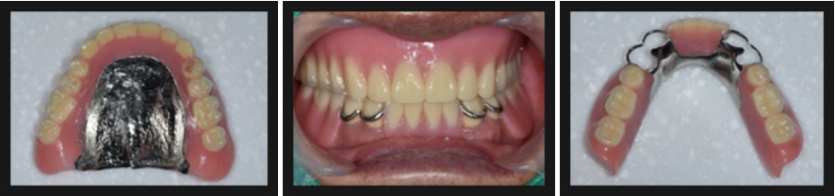

상악에 남아있는 치아는 다 발치하고 하악에도 부분적으로 치아를 남겨두고 부분틀니를 계획 하였습니다.

구리치과 인플란트치과에서는 환자분 고령이시고 드시는 약이 많아 발치는 3번에 나누어서 진행하였고,

치아를 뽑고 뼈와 잇몸이 차오르는 기간동안 임시 틀니를 사용하였습니다.

처음 사용하시는 틀니인데도 잘 적응하셔서 사용하셨습니다.